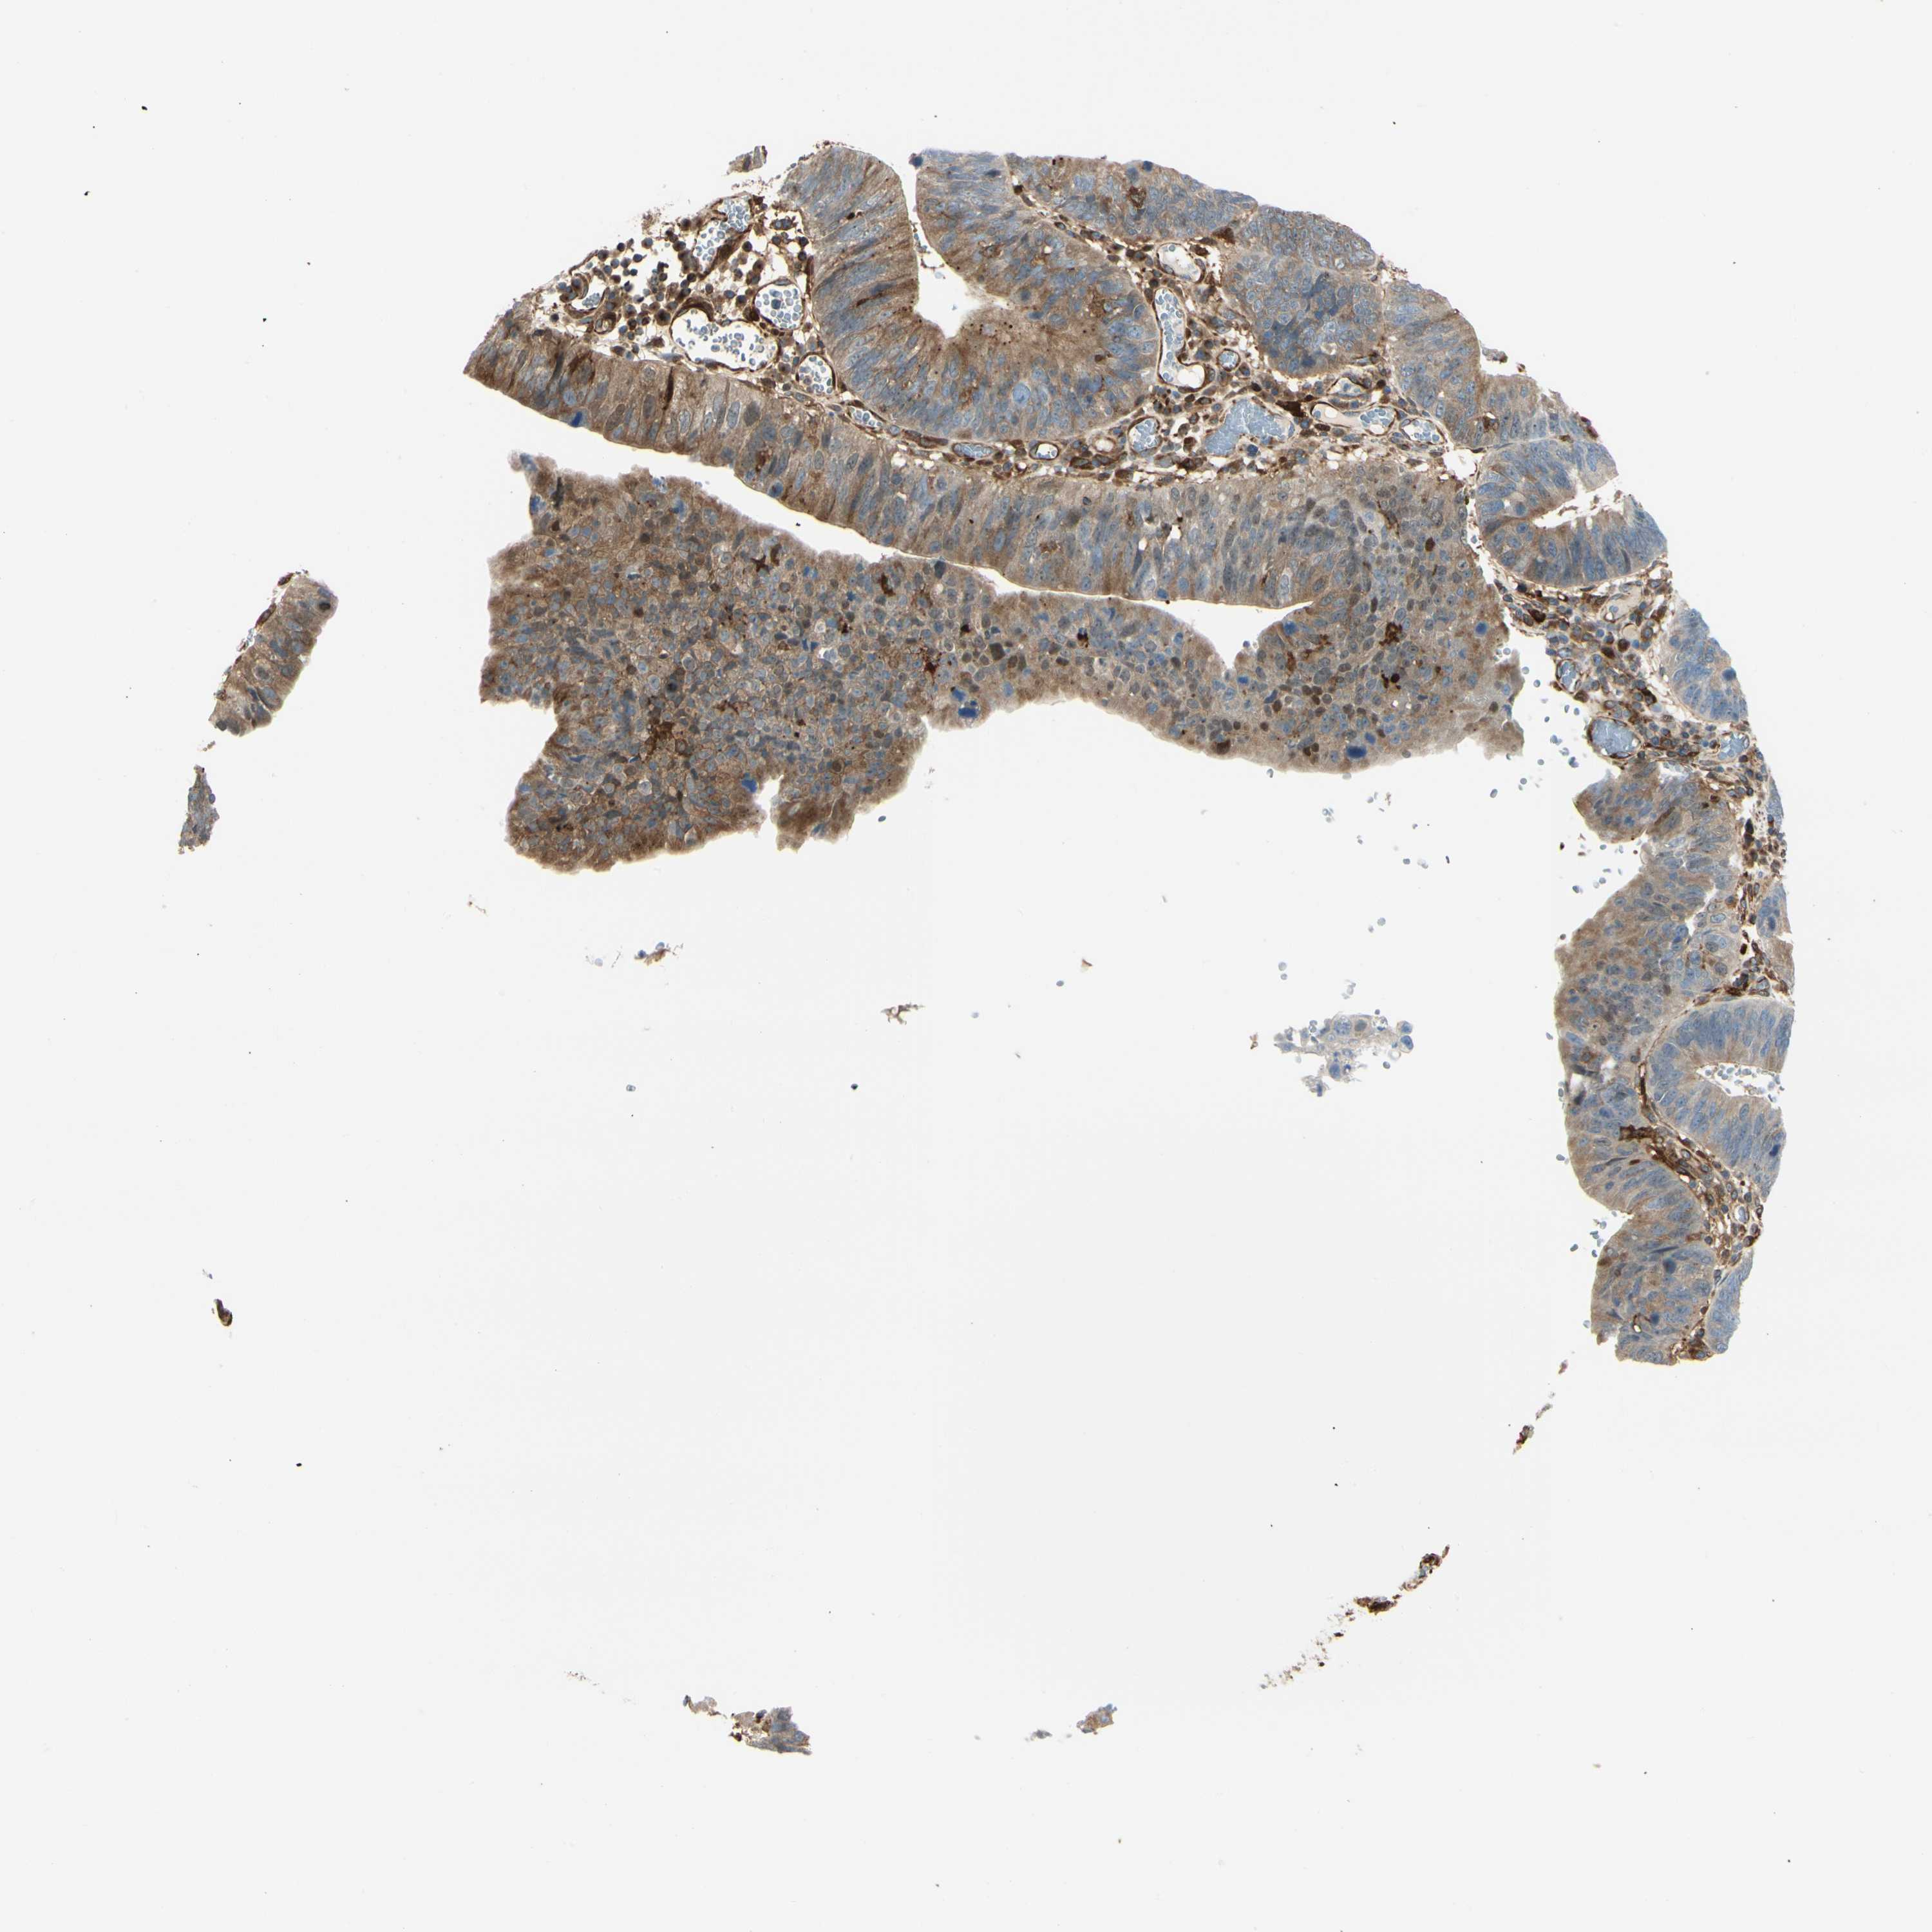

STOMACH CANCER - Protein expressioni

A mouse-over function shows sample information and annotation data. Click on an image to view it in a full screen mode. Samples can be filtered based on level of antibody staining by selecting one or several of the following categories: high, medium, low and not detected. The assay and annotation is described here.

Antibody stainingi

Antibody staining in the annotated cell types in the current human tissue is reported as not detected, low, medium, or high, based on conventional immunohistochemistry profiling in selected tissues. This score is based on the combination of the staining intensity and fraction of stained cells.

Each image is clickable and will lead to virtual microscopy that enables deeper exploration of all samples and also displays staining intensity scores, fraction scores and subcellular localization as well as patient and tissue information for each sample.

Antibody CAB008623

Staining

High

Medium

Low

Not detected

Intensity

Strong

Moderate

Weak

Negative

Quantity

>75%

75%-25%

<25%

None

Location

Nuclear

Cytoplasmic/membranous

Cytoplasmic/membranous,nuclear

Adenocarcinoma, NOS